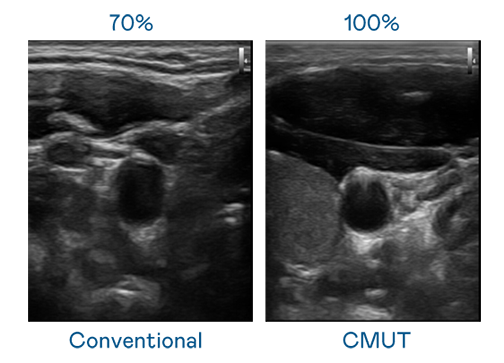

CMUT 技术是一种用电容式微机电元件来产生超音波讯号的技术。与传统 PZT 压电式技术相比,CMUT 频宽增加 30%,更宽频的超音波讯号让影像解析度大幅提升,是实现高影像品质医疗超音波扫描、促进精准医疗发展的关键技术。

大频宽带来超清晰影像

超音波影像的解析度高低,首先取决于探头能发出的讯号频宽。九游会ag CMUT 可提供高清晰的超音波讯号,提供高频宽、高灵敏度、影像纹理细节更高的超音波影像,协助医护人员缩短影像判读时间及利用精准的医疗影像进行诊断。